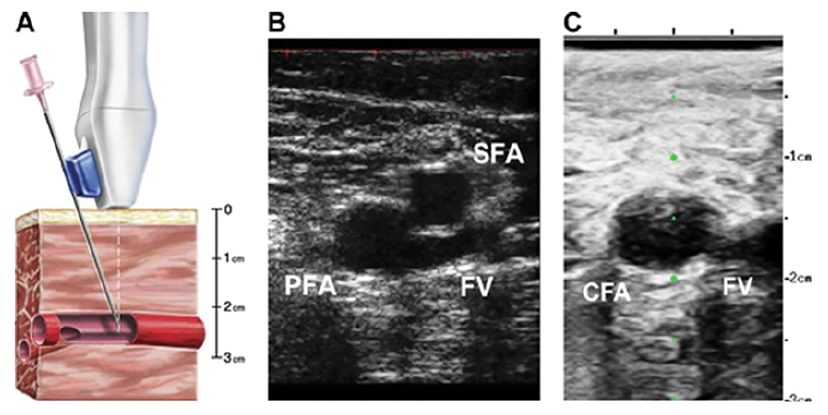

For every cath case, safe vascular access is the key to reducing morbidity and in some cases mortality. Learn both radial and femoral access well (Figures 4-5). Become an expert with ultrasound imaging, needle handling, sheath insertion, and hemostasis. Use vascular ultrasound imaging to facility safe, accurate, and quick vascular access (Figure 6). Watch how your attending overcomes the challenges of access, and how catheters are introduced and manipulated. Sometimes you may feel a need to rush through the steps. Employ the U.S. Navy SEAL Team motto, “Slow is smooth, smooth is fast”, which means that taking the time to master the fundamentals results in the best possible outcome.

For femoral artery access, use fluoroscopy for initial localization of the site for a skin nick (marked by the tip of the clamp).4 Then apply ultrasound to visualize the common femoral artery, defined by the bifurcation of the superficial femoral artery and profunda branches, and the inferior epigastric artery.